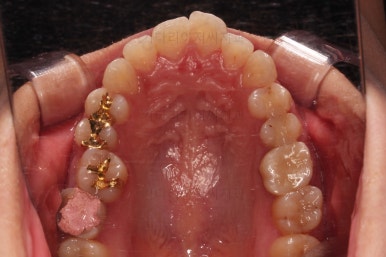

마찬가지로 초진 시 입안의 모습입니다.

입안 사진을 보니 문제점이 보이죠.

바로 어금니가 없는 상태였습니다.

물론 치열도 그리 많이 삐뚠 편은 아니고, 치아가 없으니 심플하게 임플란트를 해 넣으면 되지 않겠나 라고 생각할 수 있지만요.

나이도 많이 어리시고, 임플란트를 한다는 심리적 저항감도 있었고요.

한 번 임플란트를 해 넣으면 교정치료가 매우 힘들어진다는 점과 겸사겸사 돌출감도 개선하고자 하는 의지가 있으셔서 임플란트 없이 사랑니를 살려서 어금니 대신 쓰는 부산사랑니교정 치료를 해보기로 했습니다.